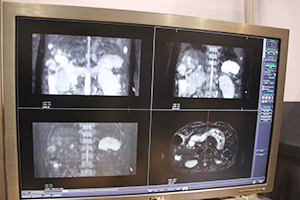

TAVR術前プランニング |

カテーテルの挿入部位から心臓までの血管径の評価を自動で行う。 |